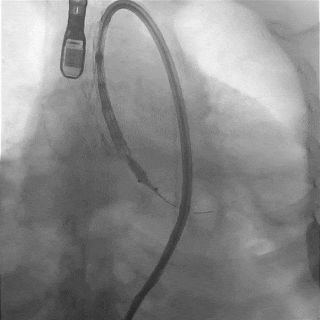

主动脉根部造影

TF29瓣膜,0位定位释放